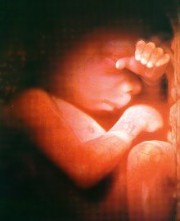

受精後6星期,人形已隱約可見。這時,胚胎的心跳每分鐘140~150下.是母親心跳的兩倍。